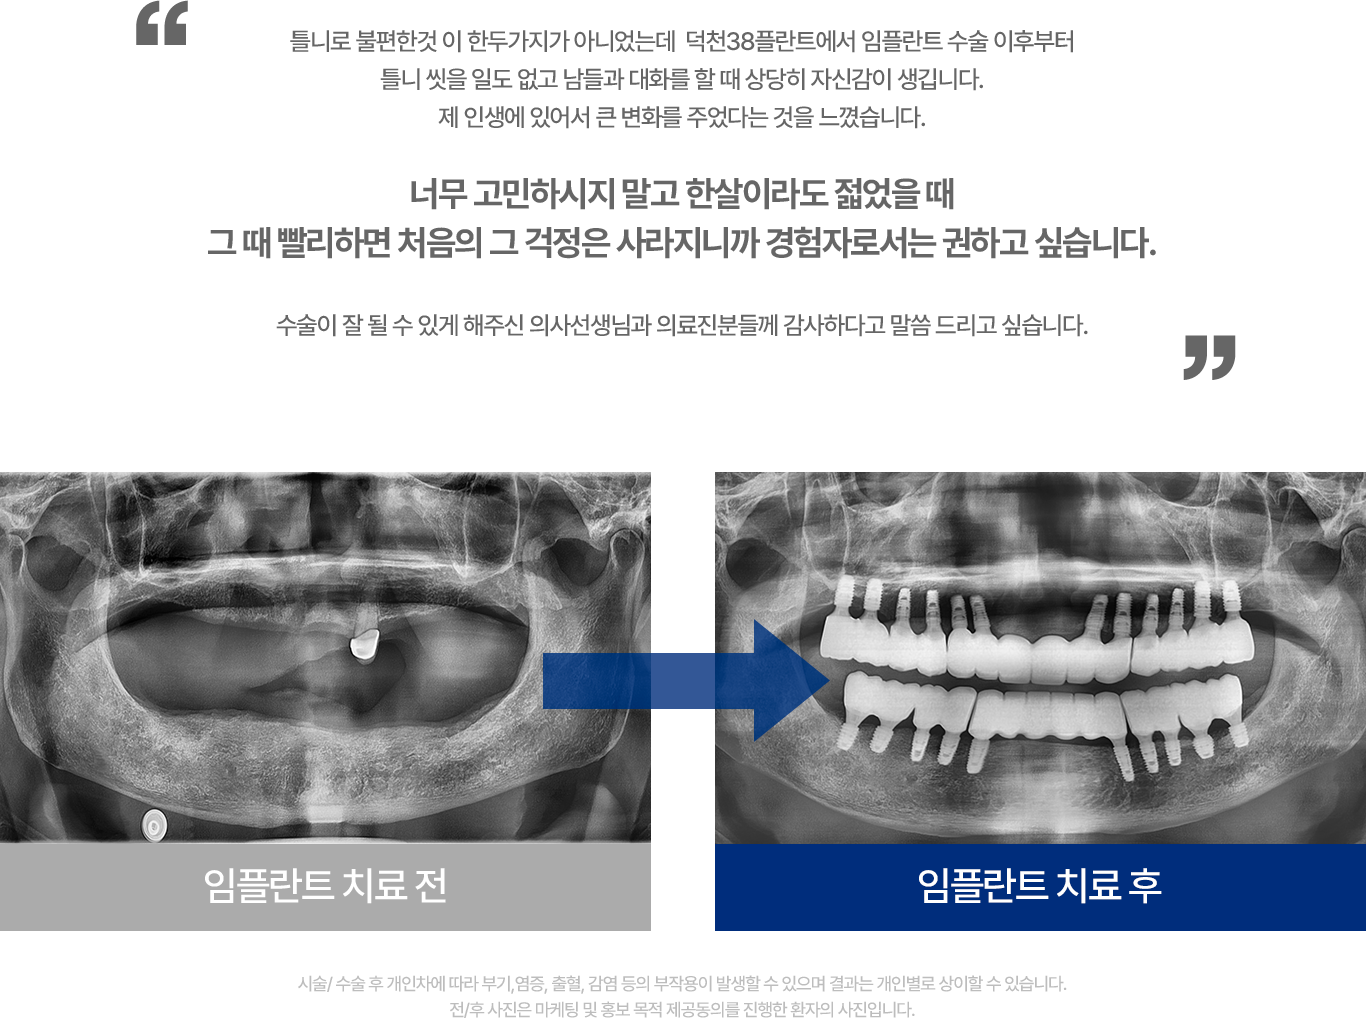

임플란트